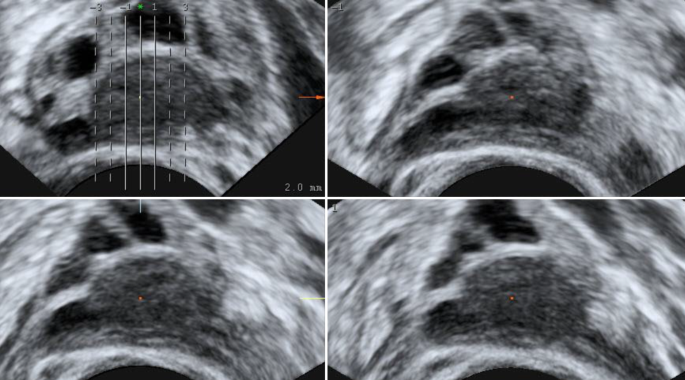

Ultraschall Der Eierstocke